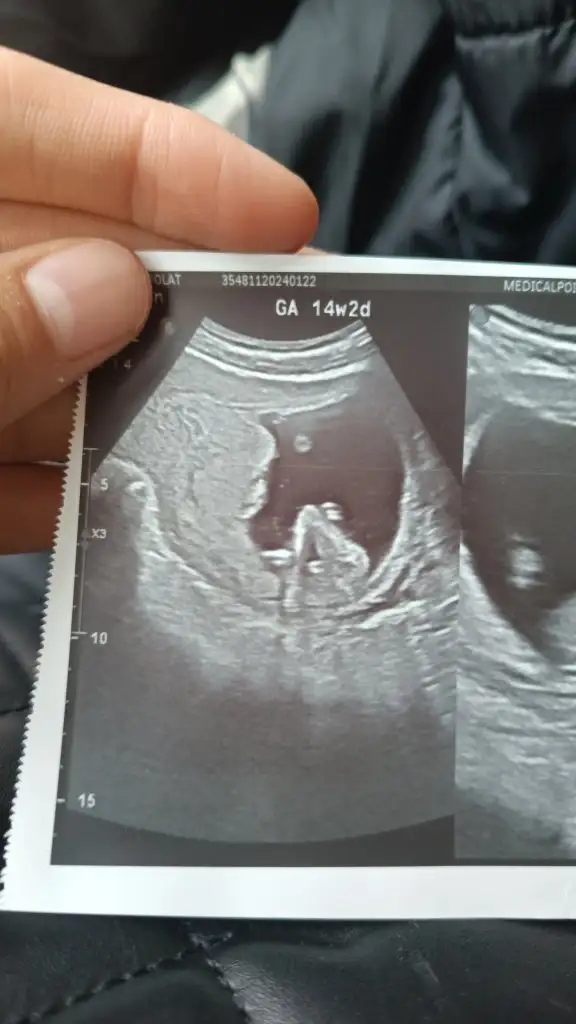

Kızlar galiba cinsiyetimiz erkek tam kesin demedi ama erkeğe benziyo pipiye benziyor dedi ultrasona göre 15 +4 çıktı sonradan haftasını yakalar dedi sen adet tarihine göre takip et dedi

Eklentiler

• IMG-20240328-WA0001.webp

IMG-20240328-WA0001.webp

22,8 KB · Görüntüleme: 59